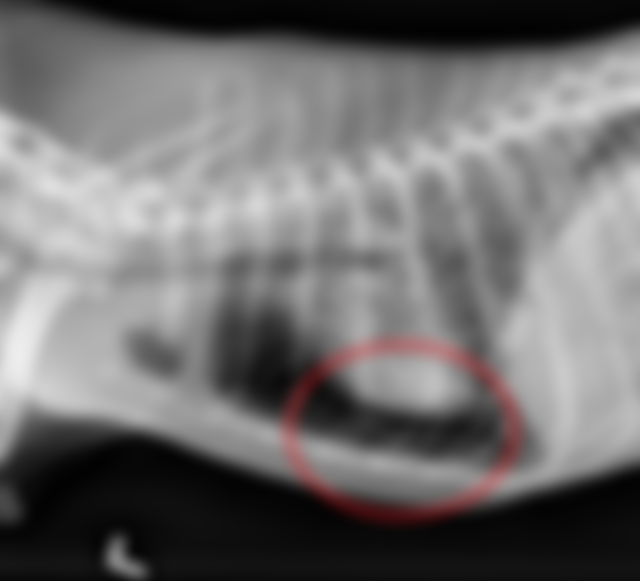

48.13歲哈士奇(Husky)犬呈現消瘦、虛弱、喘、食慾廢絕、尿失禁,胸腔影像如下圖,下列敘迹何者正確?

(A)後肺葉血管直徑變大

(B)有氣胸(pneumothorax)

(C)有胸膜腔積液 pleuraleffusion)

(D)心臟變小,可能和嚴重脫水有關